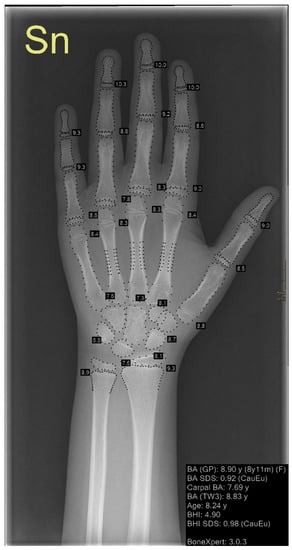

Only a few systems have been commercialized, one of which is BoneXpert, developed in 2008, which has been progressively upgraded and extended to estimate bone maturation until 19 years (Figure 3).

Figure 3. Example of an X-ray analyzed with BoneXpert. Standard radiograph of left hand and wrist. BoneXpert automatically recognizes bone segments and analyzes the hand–wrist bones. The analysis results are shown in the black box on the right, where bone age is calculated through both GP and TW3 methods.

BoneXpert is currently used in Europe to automatically extract features such as the shape and density of hand–wrist bones, reducing reading times by 87% [70]: it automatically reconstructs the borders from X-ray images of the hand and wrist and calculates “intrinsic” bone ages for each of 13 bones (radius, ulna, and 11 short bones). Finally, BoneXpert converts intrinsic bone ages into TW or Greulich–Pyle GP bone ages. Images with abnormal bone morphology or extremely poor image quality are automatically rejected by the bone reconstruction method [68]. The tool has been demonstrated to be significantly more precise than the traditional application of the GP method and its performance has been improved with the new updates. For instance, version 2.1 achieved an overall root-mean-square deviation of 0.38 years versus 0.71 for the first version [68,70].